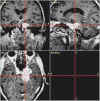

TC preoperatoria

TC postoperatoria

RM preoperatoria

RM postoperatoria